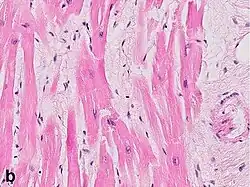

Under the microscope, myocardial infarction presents as a circumscribed area of ischemic, coagulative necrosis (cell death). On gross examination, the infarct is not identifiable within the first 12 hours.[22]

Although earlier changes can be discerned using electron microscopy, one of the earliest changes under a normal microscope are so-called wavy fibers.[23] Subsequently, the myocyte cytoplasm becomes more eosinophilic (pink) and the cells lose their transversal striations, with typical changes and eventually loss of the cell nucleus.[24] The interstitium at the margin of the infarcted area is initially infiltrated with neutrophils, then with lymphocytes and macrophages, who phagocytose ("eat") the myocyte debris. The necrotic area is surrounded and progressively invaded by granulation tissue, which will replace the infarct with a fibrous (collagenous) scar (which are typical steps in wound healing). The interstitial space (the space between cells outside of blood vessels) may be infiltrated with red blood cells.[22]

These features can be recognized in cases where the perfusion was not restored; reperfused infarcts can have other hallmarks, such as contraction band necrosis.[25]

| Myocardial histologic parameters (HE staining)[26] | Earliest manifestation[26] | Full development[26] | Decrease/disappearance[26] | Image |

| Stretched/wavy fibres | 1–2 h |

| Coagulative necrosis: cytoplasmic hypereosinophilia | 1–3 h | 1–3 days; cytoplasmic hypereosinophilia and loss of striations | > 3 days: disintegration |